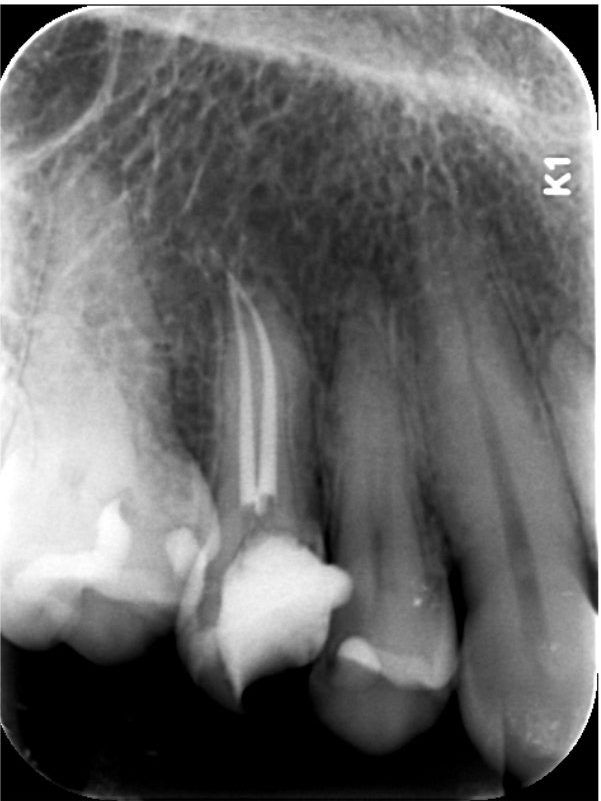

This case used the Bassi Logic 25/.05.